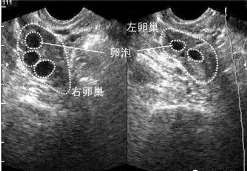

试管婴儿有优势卵泡还不够,优质卵泡做试管的成功率 临床上将发育成熟、大小在12~18mm左右、形状浑圆且均匀的 […]

试管取卵多大卵泡能取[试管取卵要多久] 1、试管婴儿促排卵期间,医生会通过B超对卵泡发育情况进行监测,卵泡大小 […]

促排17天卵泡才长到11?促排打绒促17天卵泡才长到11mm是怎么回事?下面我们就来具体介绍下。 正常情况下, […]

优势卵泡排出时间因人而异 相信很多备孕的姐妹都知道在排卵期同房能增加怀孕的几率。月经准确的姐妹排卵时间比较固定 […]

卵泡排后会留下空壳的原因?那本文就这个问题以卵泡不长内膜长什么原因为大家详细介绍一下。 卵泡排后会留下空壳的原 […]